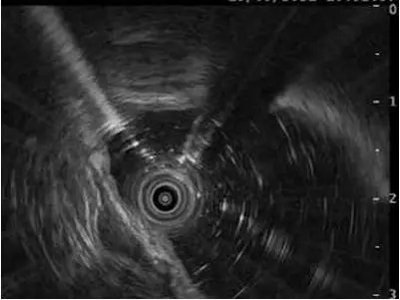

通俗来讲,超声内镜也叫内镜超声(EUS),就是一种在胃肠里做的超声,有别于把超声探头放在皮肤表面的方法,这种超声探头是放在胃肠道里的。

▲ 超声微探头

▲ 环扫型超声内镜

▲ 扇扫型超声内镜

那么怎么把探头放进去呢?那就要借助于内镜了,根据病灶的部位和大小,可以通过内镜上的工作钳道把超声微探头送进胃肠道,或者选择前端本身自带超声探头的内镜。